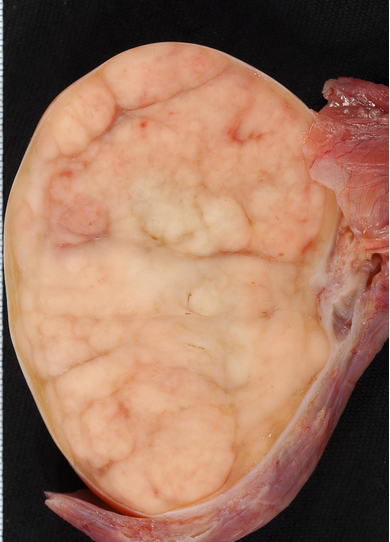

Kəskin mediastinit əksər hallarda ikincili xəstəlikdir, başqa sözlə, döş qəfəsi və ya ətraf orqanlarda baş verən zədələnmə və ya irinli iltihabi xəstəliklərin ağırlaşmasıdır (Şəkil 8).

Şəkil 8. Kəskin mediastinitin səbəbləri və patogenezi